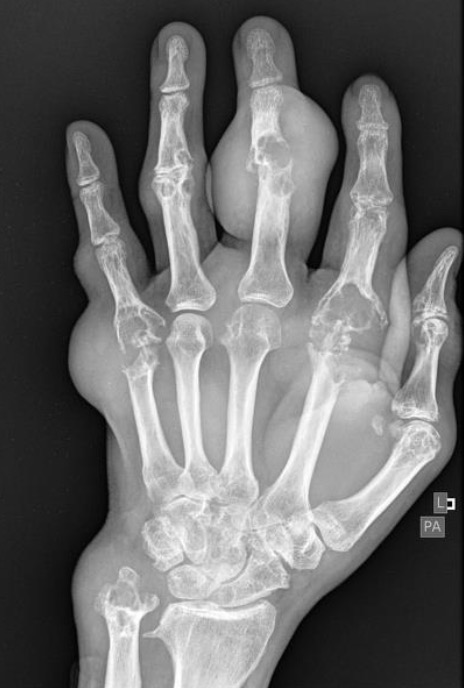

Gout ⭐

Soft tissue swelling

Well defined, punched-out erosions (rat bite)